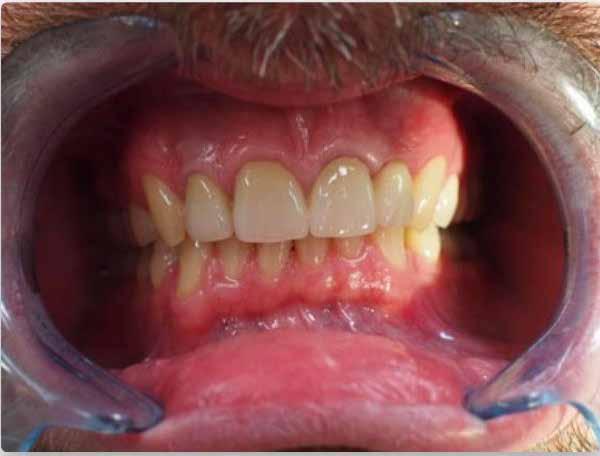

periimplantáris szövetstabilitás és a páciens elégedettsége az

4 Tartalom IMPLANTOLÓGIA „A tapasztalataim alapján egy kicsit óvatos vagyok…” 8 Rövid és keskeny implantátumok aktuális konszenzus kérdései 14 Periimplantáris csontdefektusok minimálinvazív rekonstrukciója és augmentációja autológ csonttal 20 Szájüregi probiotikumok és implantológiai jelentőségük 26 Szóló foghiányok ellátása extra rövid implantátumok és transzmukozális fej segítségével – 2:1 felépítmény/ implantátum arány mellett 30 Kezelhető-e a periimplantitis nem sebészi úton? 34 Az implantáció sikerességének növelése az alveolus kettős hullámhosszú lézeres előkezelésével 40 Alpha Implant hírek 44 Geistlich Bio-Oss Collagen és az „L-Shape” technika 45 A sebészi technika és a PRF szerepe az alveoláris csont és a mukogingivális struktúrák megőrzésében III 48 A modifikált, koronálisan vagy laterálisan eltolt tunnel egyszerű vagy multiplex ínyrecessziók kezelésére 56 A

implantátumbeültetés után az esztétikai területen 60 Erős fogak és egészséges száj – meggyőző mosoly 70

azonnali